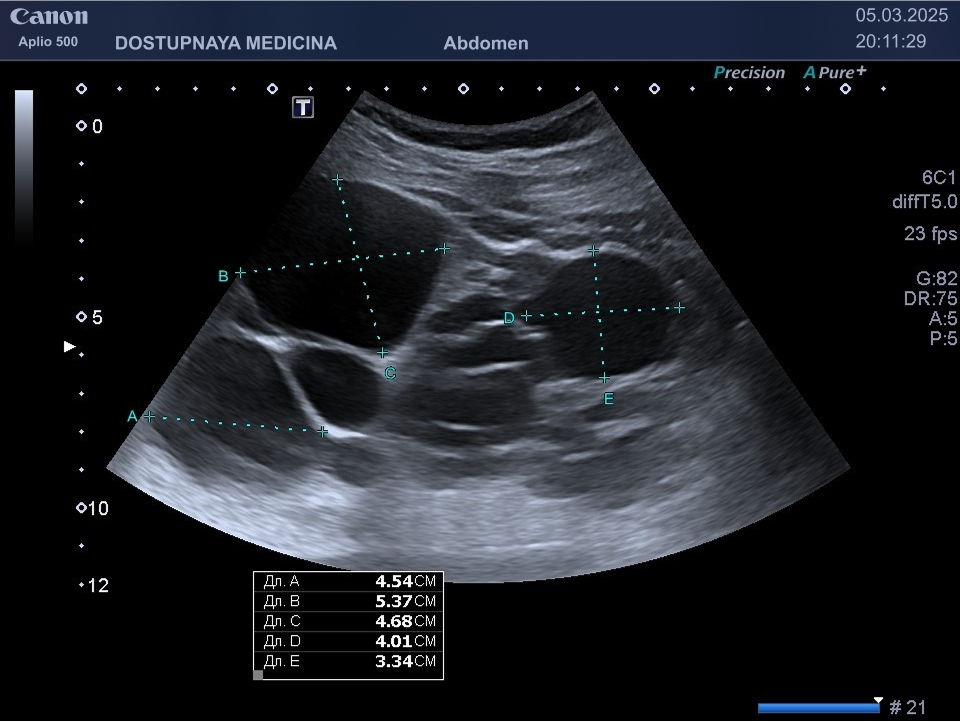

Чаще всего кисты почек протекают бессимптомно и являются случайной находкой во время ультразвукового исследования. При увеличении кисты в размерах может появиться боль в поясничной области в результате раздражения образованием нервных окончаний почки. Большая киста может сдавливать сосуды почек, приводя к нарушению кровотока в органе вплоть до полной гибели органа с развитием почечной недостаточности. Киста, локализованная в почечном синусе, может сдавить лоханку и чашечки почки, что приводит к нарушению оттока мочи вплоть до гидронефротической трансформации почки с полной утратой её функции. Поэтому очень важен периодический контроль размеров кисты не реже 1 раза в 6-12 месяцев.

Сонографическими критериями поликистозной болезни почек при наличии этой болезни у родителей следует считать наличие двух и более кист в одной или обеих почках в возрасте меньше 30 лет, наличие двух и более кист в каждой почке в возрасте 30-59 лет и наличие четырёх кист в каждой почке в возрасте 60 лет и более.

В моей практике неоднократно встречались пациенты, у которых ранее находили две или три небольшие кисты почек, а уже через три года я выявлял у них при ультразвуковом исследовании полную кистозную трансформацию одной почки и множественные кисты больших размеров во второй почке.

Кисты небольших размеров (до 3 см), как правило, не требуют никакого лечения, необходимо лишь контролировать размеры и количество кист не реже 1 раза в 6-12 месяцев. Кисты от 3 до 5 см можно пунктировать и дренировать под контролем УЗИ с последующим введением в них склерозирующего препарата. Более крупные кисты (больше 5 см), как правило, иссекают лапароскопически. Медикаментозного лечения кист на данный момент не существует.